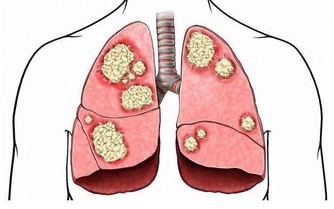

3、血便

如果便中帶血請趕快就醫!血便有可能是因為痔瘡,也有可能是癌症造成的。